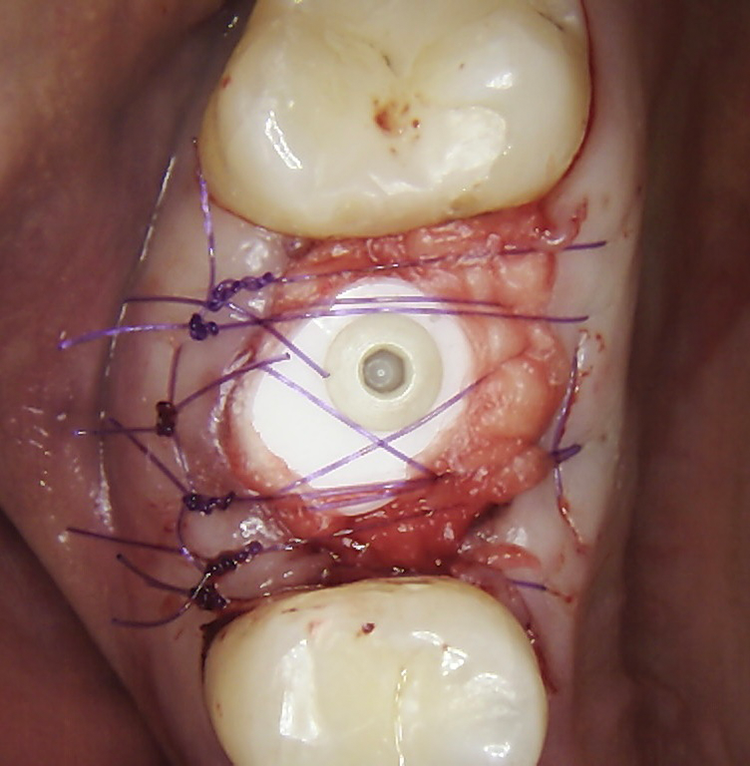

Die Augmentation des Alveolarkamms richtete sich nach der Größe des Defekts. Der Kollagenblock (Condress 5 x 5 cm, Smith & Nephew) wurde auf die erforderliche Größe zugeschnitten und am Alveolarkamm sowie um das Implantat herum verdichtet. Zur Stabilisierung der A-PRF-Matrizen und des Kollagenblocks sowie zur Repositionierung des Lappens wurde eine nicht resorbierbare monofile Naht (Atramat® 5-0, Mednaht) verwendet. Vor der prothetischen Belastung mussten die Implantate 4–8 Wochen einheilen.

Bei dem balkonförmigen Implantat blieben die Alveolarkämme und der Kronenansatz erhalten (Abb. 4c und d). Der Spalt zwischen dem Implantat und der bukkalen Lamelle wurde mit A-PRF und einem Kollagenblock aufgefüllt, so dass keine zusätzliche Knochenaugmentation erforderlich war. Zusätzlich wurden PRF-Matrizen um, über, unter und neben dem Implantat im Knochen-Implantat-Raum positioniert (Abb. 1 bis 4b). Außerdem kam eine optionale Einheilscheibe (6 x 8 mm) zum Einsatz, um das Kollagen und die PRF zu sichern (Abb. 3b). Die Implantate zeigten bei einem Drehmoment von 35 Ncm Stabilität, welche mit dem Periotest-Gerät von Medizintechnik Gulden getestet wurde. Die Werte des Implantatstabilitätstests, die im Bereich von –8 bis 0 lagen, wurden als ideal für die Belastung angesehen (Tab. 3).

Abb. 2: Repräsentativer Fall von ABH Grad B Septus Typ II. a) Ansichten vor der Installation. Röntgenaufnahme der periapikalen Läsion an einem wurzelkanalbehandelten Molaren und klinische Ansicht der Typ-II-Socket nach der Extraktion. b) Die Ansichten nach der Installation zeigen das Implantat innerhalb des interradikulären Septums und das über dem Implantat platzierte A-PRF. c) Nachuntersuchungen nach 10 Tagen bzw. 2,1 Monaten. Die Röntgenaufnahme zeigt die Knochenbildung zwischen der Sinusmembran und dem apikalen Teil des Implantats. d) Jüngste Nachuntersuchung nach Einsetzen der Prothese.

Abb. 3: Repräsentativer Fall von Grad A Typ I. a) Präoperative Ansicht. Röntgenbild der periapikalen Läsion an einem wurzelkanalbehandelten Molaren. Die Höhe des Alveolarknochens zeigt Grad A an. b) Klinische und radiographische Ansicht der Implantatinsertion unter Verwendung einer Einheilscheibe mit großem Durchmesser (6×8 mm). A-PRF wurde um das Implantat und unter der Scheibe platziert. c) Nachuntersuchung nach 5,9 Monaten vor und nach der Zementierung und Aufbereitung. d) Jüngste Nachuntersuchung nach Einsetzen der Prothese